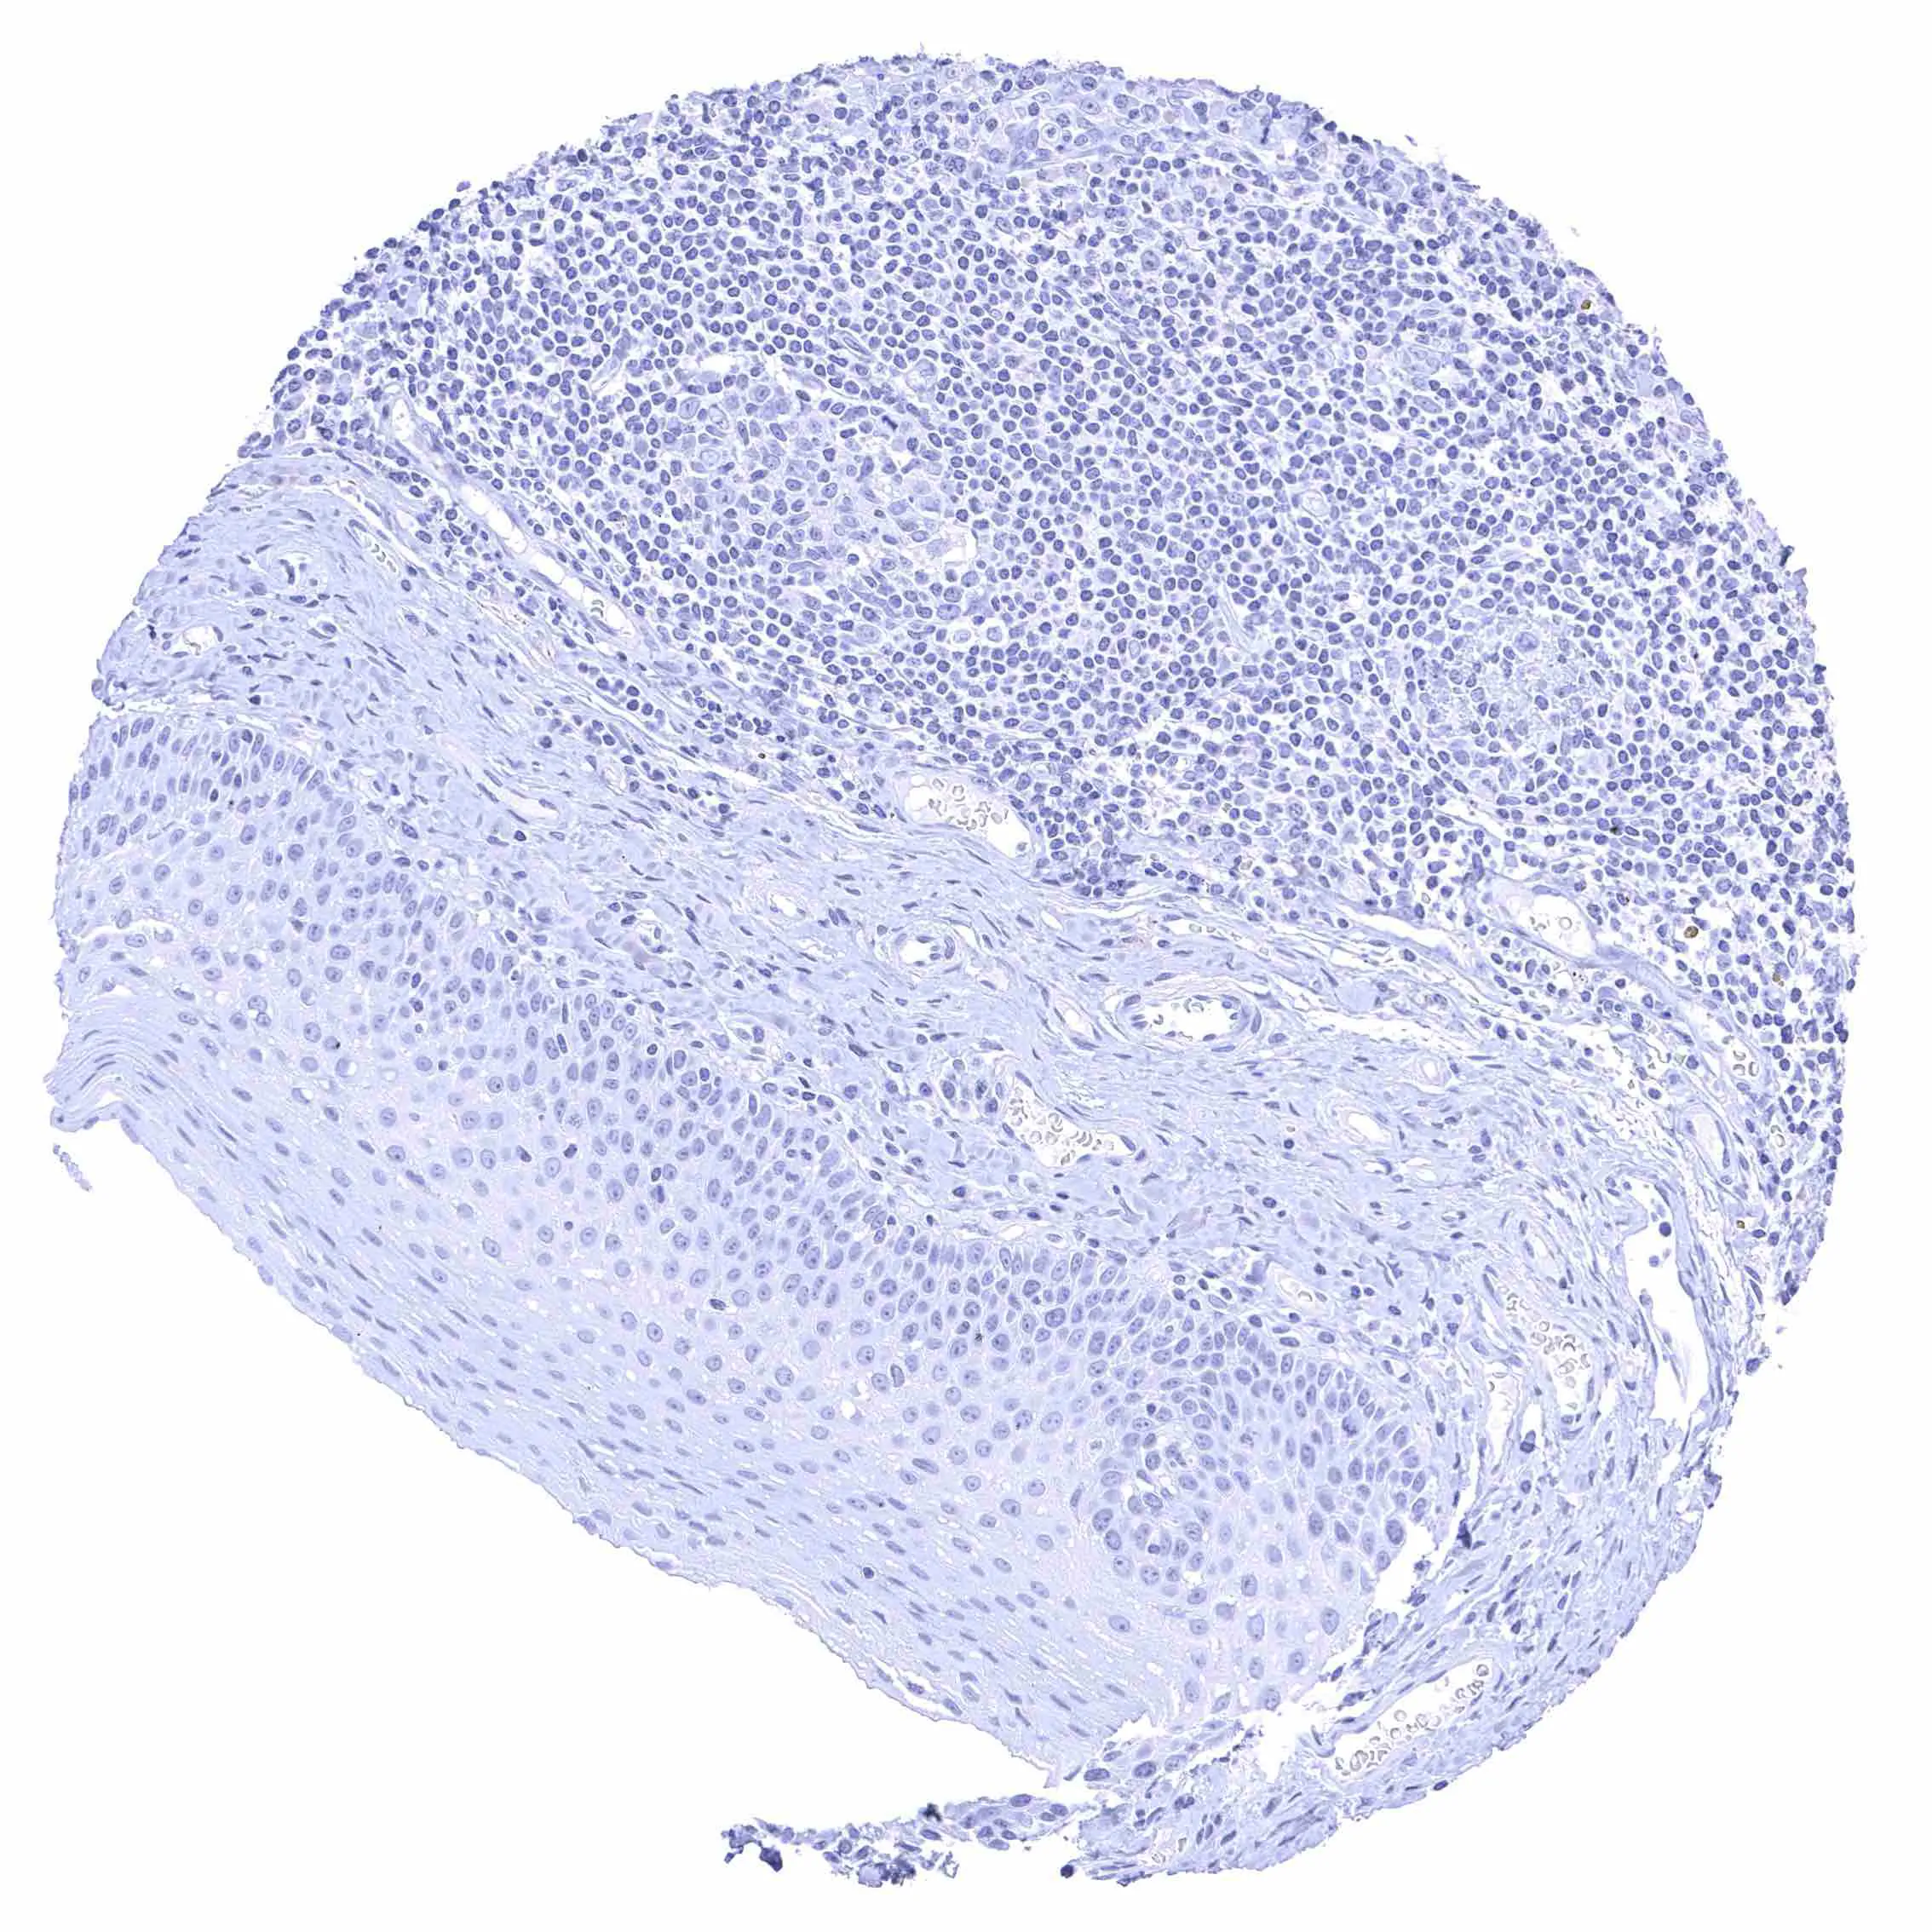

Uterus, ectocervix